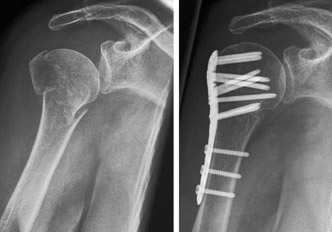

Behandlungen von Schulter-, Ellbogen- und Handgelenks-verletzungen sind oft sehr anspruchsvoll und komplex. Deshalb ist mit einer längeren Erholungsphase in vielen Fällen bis zu 6 Monaten und länger zu rechnen, beispielsweise bei Operationen bei Schulterluxationen und Instabilitäten am Schultergelenk, Schultergelenksarthroskopien bei Einklemmungssyndromen, Rekonstruktion der Rotatorenmanschette, Kunstgelenk-ersatzoperationen an der Schulter. Die Entwicklungen auf diesem Fachgebiet sind enorm vorangeschritten, sodass heute viele Eingriffe in entsprechender arthroskopischer oder minimal-invasiver Technik durchgeführt werden können. Dies führt in der Regel zu bedeutend kürzeren Spitalaufenthalten und schnellerer Erholung.

Die  wichtigsten Verletzungen und Erkrankungen an Schulter, Ellbogen und Hand: